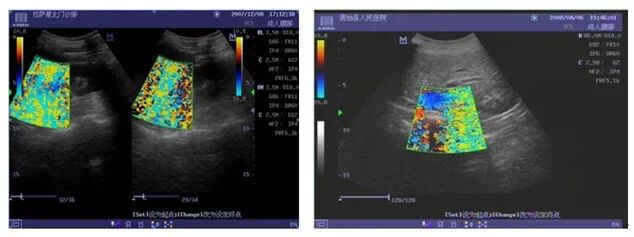

1、超声探头干扰(DC-6)

原因一:探头线缆屏蔽层断裂,致使干扰电磁场被引入出现图像干扰问题。

改进措施:2010.2月改用耐拉拽、弯曲强度更高的探头线缆。

原因二:探头屏蔽线与信号地方式不合理。

改进措施:改善探头蔽屏线的连接方式。